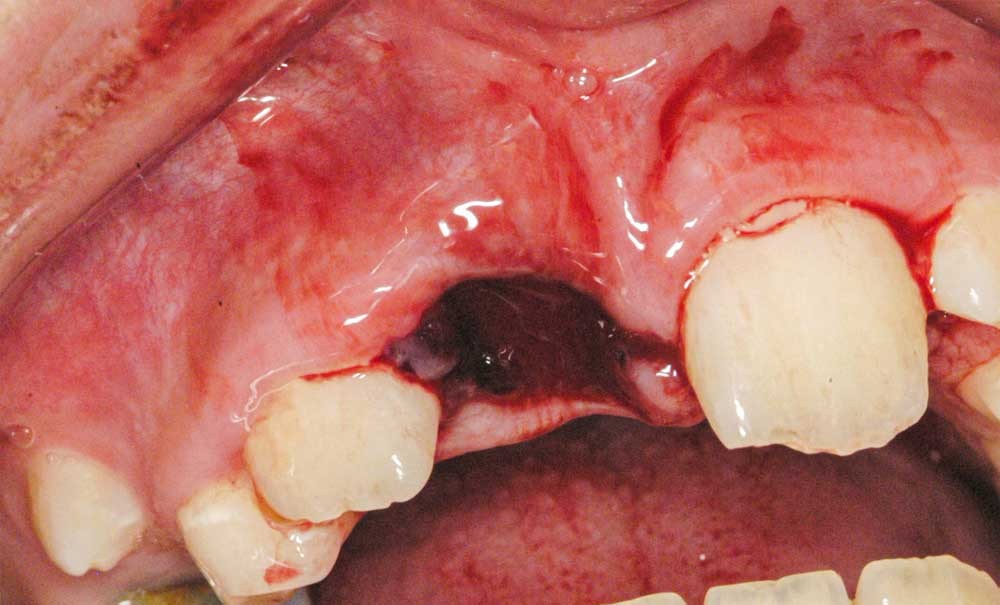

Cas 2

Adolescente de 17 ans ayant trois dents (12, 11, 21) expulsées lors de travaux aux champs (fig. 5), ainsi qu’une luxation latérale de la 13. Elle est adressée par les urgences du CHU de Rennes et la consultation a lieu 6 heures…